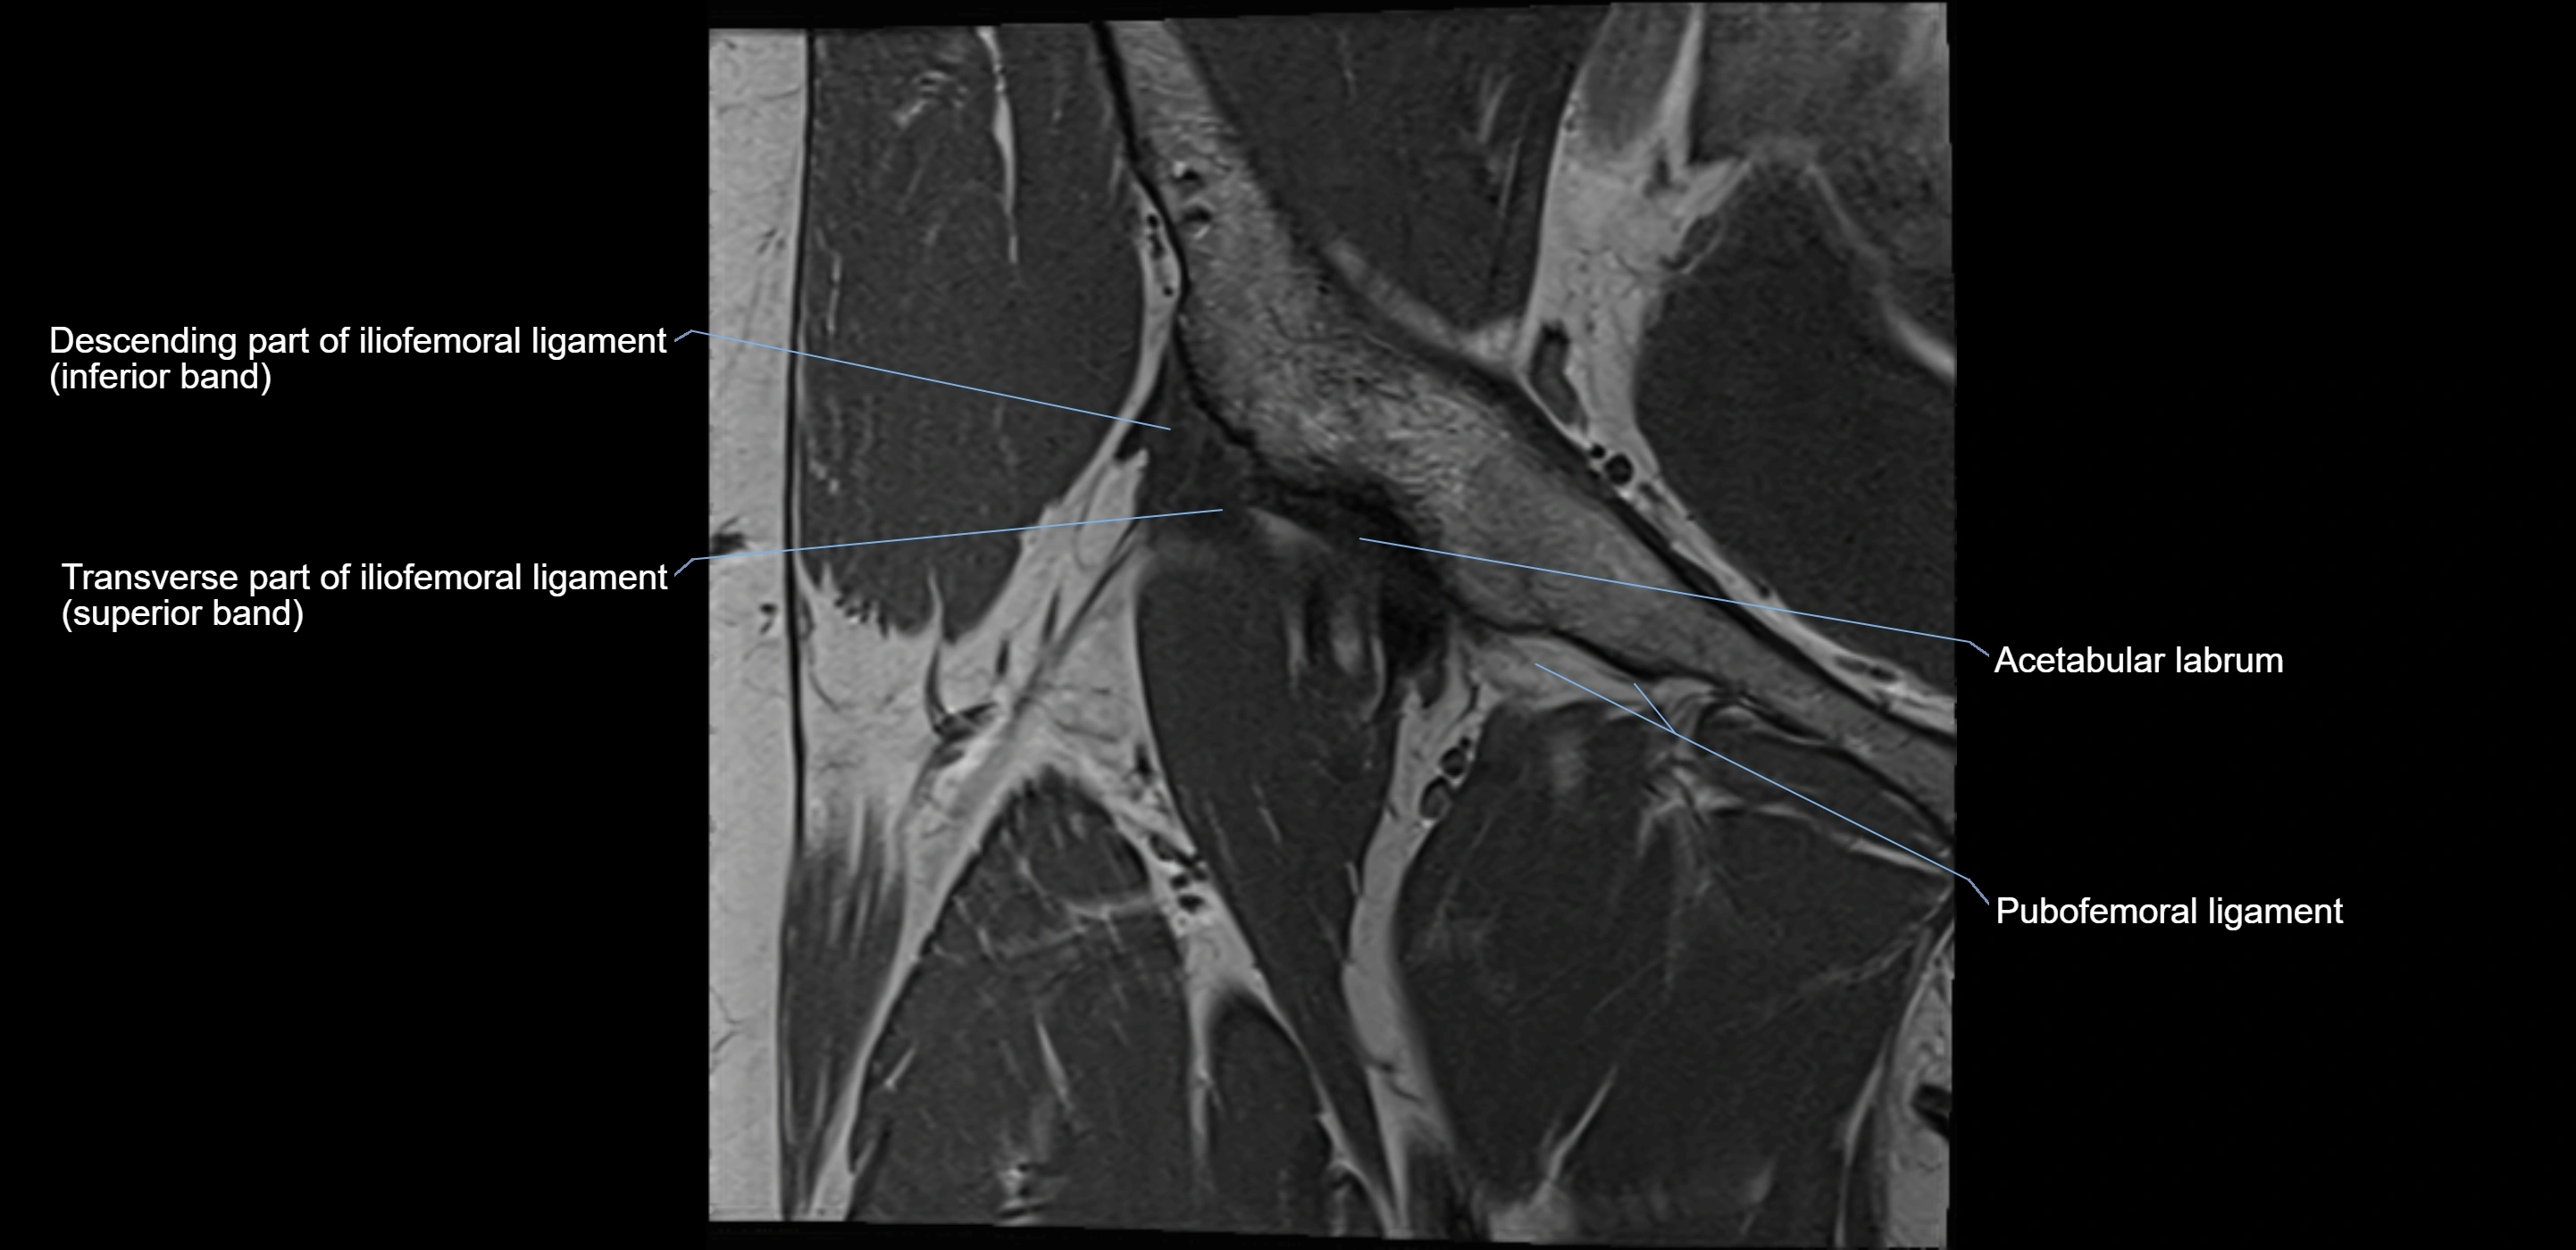

MRI image

image